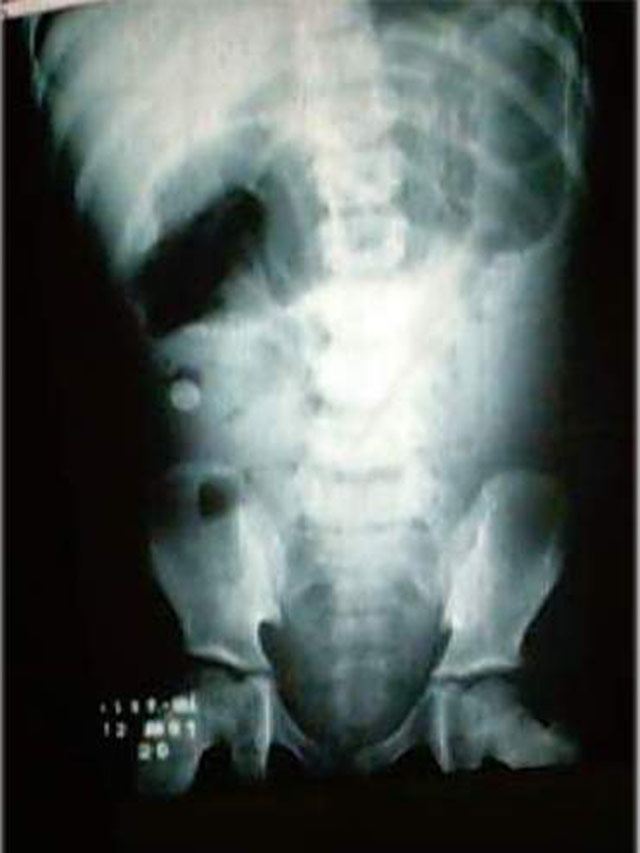

No Rx abaixo vemos distensão de alças de delgado

com presença de imagem radiopaca

na fossa ilíaca direita.